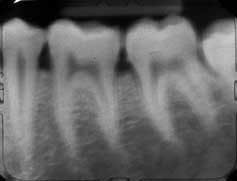

Repeat the process for each of the next three films. If all the basic rules have been followed, you will record the teeth designated for each film with a full view of the clinical crown, full view of the root and surrounding bone and tissue, and no interproximal overlapping.

Treat the posterior segments in a similar mesio-distal manner. The long axis of the film is placed in the Styrofoam holder (white side always toward the teeth) so that the film follows the occlusal plane of the arch. Again, placement of the film is of paramount importance in securing diagnostic quality X-rays. There is no excuse for improper placement of films in the arch by the clinician.

• Properly imaging the molar view in the arch depends on placing the film opposite the third molar area. This is done in a similar way as is used for the bicuspid view, except that the mesial of the film as it is placed in the mouth must be at the middle of the first molar. The patient is biting lightly on the Styrofoam holder. The angle of the X-ray head is set at 20 to 25 degrees in the upper arch. Once again, it's important to develop the ability to bring the face of the tube parallel to the second and third molars and aim the tube to send the beams perpendicular to the film to avoid overlapping. If the film is viewed as being entirely within the face of the tube, you will avoid cone cutting and interproximal distortion. This gives you a clear view of the second and third molar area, the distal half of the first molar and surrounding bone and soft tissue.

The most common errors seen are the overlapping of bicuspids on the cuspid view. This occurs because the film has not been placed with the cuspid in the middle of the film, and the head of the X-ray is turned so that the beam is casting the shadow from the distal through the bicuspids onto the cuspid, or because the beam is casting the shadow from the mesial through the cuspid overlapping on the bicuspids. Remember, you are aiming the beam like a rifle, and the beam is a bullet that must pass through the face of the tooth or teeth you want to X-ray. The open face of the tube must be parallel to the face(s) of the teeth being X-rayed.